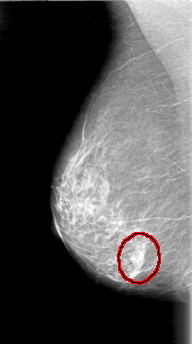

D_4001_1.LEFT_CC

RIGHT_MLO LINES 5146 PIXELS_PER_LINE 2866 BITS_PER_PIXEL 12 RESOLUTION 43.5 OVERLAY

FILE: D_4001_1.RIGHT_MLO.OVERLAY

TOTAL_ABNORMALITIES 1

ABNORMALITY 1

LESION_TYPE MASS SHAPE OVAL MARGINS OBSCURED

ASSESSMENT 0

SUBTLETY 5

PATHOLOGY BENIGN

TOTAL_OUTLINES 1

BOUNDARY